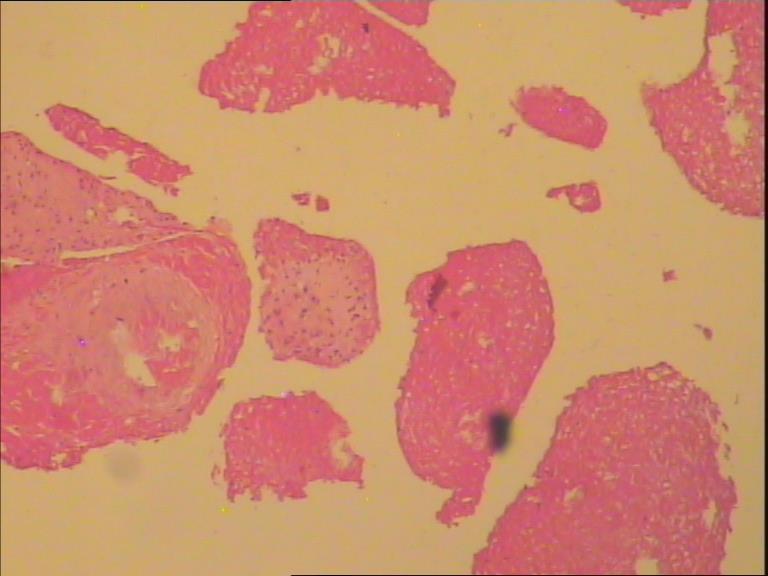

骨巨细胞瘤1级

膝关节置换术后7年,疼痛6月。 术中见关节假体周围大量增生肉样、葡萄状组织。是否有骨质浸润手术医生说不清楚,X片未见骨质浸润。

膝关节腔内肿物

灰白组织一堆直径7cm,部份组织呈葡萄样。

切片内可见坏死组织 图9

那些颗粒状物是假体脱下来的碎屑,巨细胞首先考虑是反应性的。

会诊意见:见大量组织细胞,多核j巨细胞反应,未见明确肿瘤性病变。